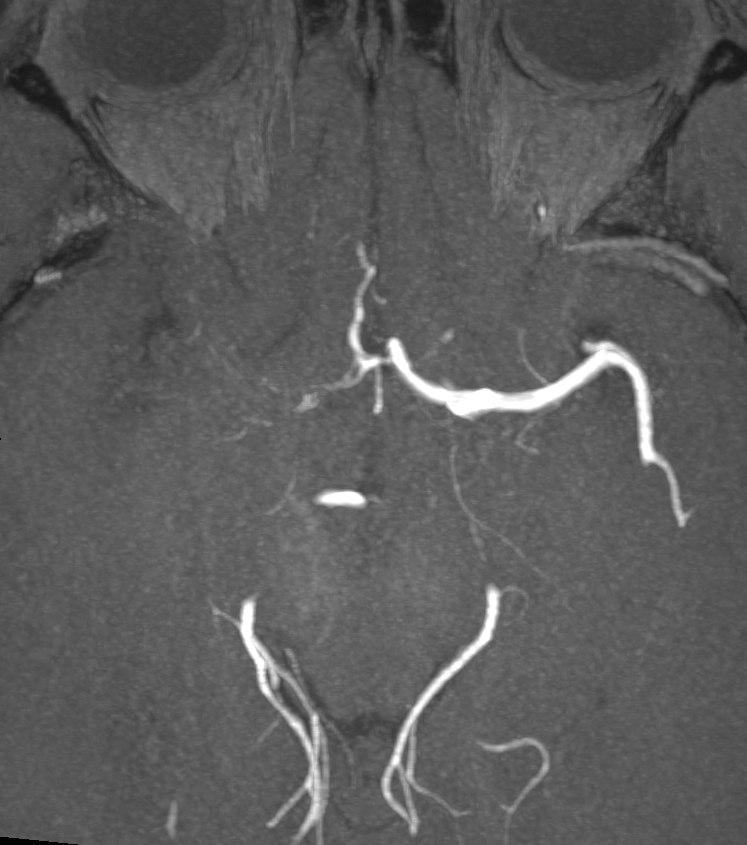

- Magnetic Resonance Angiography (MRA):

- Focal or multifocal stenosis of cerebral arteries

- Beading appearance of affected vessels

- 50-year-old patient presented with visual disturbance and left sided weakness.

- CSF PCR was positive for VZV.

- MRI showed multiple left MCA territory infarcts.

- There wasthick eccentric enhancement on the right MCA but no stenosis initially.

- After 5 months and following steroid therapy, the enhancement associated with the vasculopathy regressed but a severe long segment stenosis developed. This only slightly improved (trace of flow related signal) on further follow-up MRA (not shown).